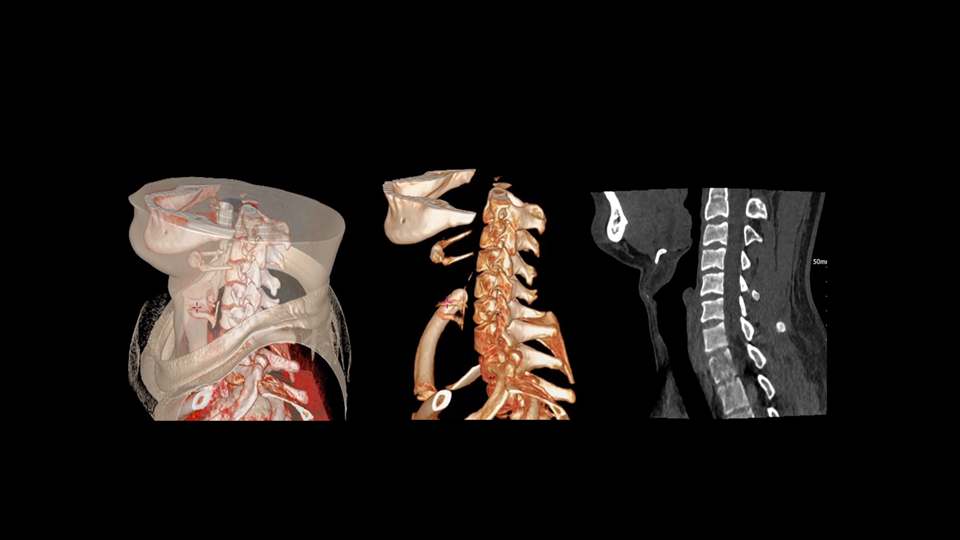

CT技术正经历一场从“静态看清解剖”到“动态看懂功能”的深刻变革。双宽体双源CT系统 uCT SiriuX®,首度融合宽体探测器与双源架构,在时间、覆盖与精准度上实现全面飞跃。从心脏搏动到全身脏器,从细微解剖到动态变化,皆清晰可见。技术之上,更为看见生命每一次律动。

uCT SiriuX® 依托16cm超宽探测器与双源能谱技术,实现真正意义上的全身高清能谱成像。单次扫描同步获取灌注、能谱等多维定量参数,精准解析组织特性与病灶成分,为临床决策提供更深层次的诊断依据。